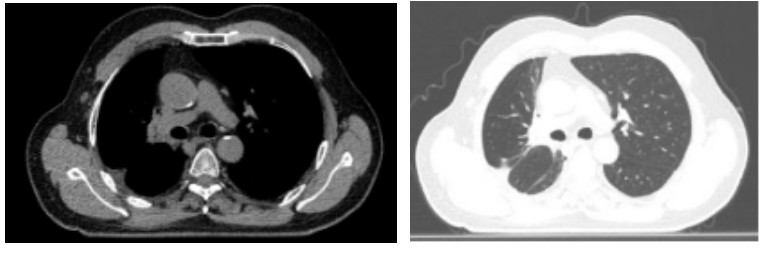

Figure 3. Two years after carbon ion therapy for chest tumor